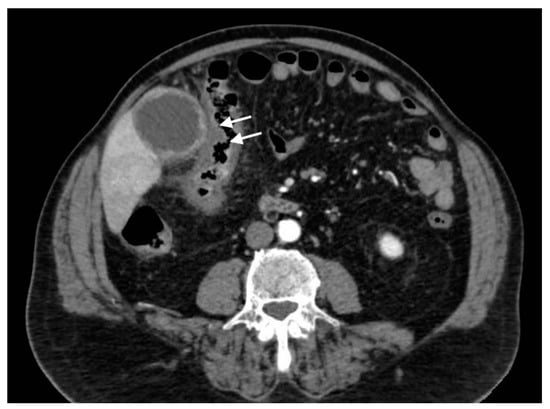

Acute portal vein thrombosis is an uncommon condition caused by the formation of a thrombus within the portal vein, as the inflammatory insult persists. Besides acute cholecystitis, it could be diagnosed as a complication of many other conditions, such as diverticulitis, urinary and pelvic infections, and malignancies [23,24]. Symptoms may be subtle, often masked by the underlying condition. CT and US are the main modalities for the acute assessment of PVT. The lack of enhancement within the vein lumen and an enlarged portal vein are the two main classic imaging CT features [24,25]. CT, unlike US, is also able to evaluate the extension of the thrombus and to detect associated findings, such as hepatic hyperemia (Figure 10), or complications, such as enteric ischemia or intra-abdominal collections [24]. Suppurative thrombosis of the portal vein, also known as pylephlebitis, is a life-threatening condition that requires early diagnosis and therapeutic assessment. The exact pathogenesis is not well known, but it is proven that specific bacterial species, such as Bacteroides Fragilis, play a key role in favoring a protrombothic state [26] and the clinical features of sepsis. As regards PVT, CT evaluation is meaningfully superior to ultrasonography for the diagnosis. Consequent to hepatic artery overflow due to PVT occlusion, transient contrast enhancement of the adjacent hepatic parenchyma during the arterial phase may occur, as well as hepatic microabscesses (Figure 11) [27]. Although not seen in most cases, CT may detect the presence of air within the thrombus as a hypodense focus within the thrombosed PV [24].

Figure 10.

Right portal vein thrombosis: extensive right portal vein hypodensity subsequent to an intraluminal thrombus formation (black arrows) with hepatic hyperemia (white arrows).